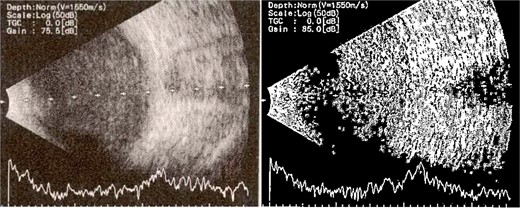

Patient 2: A 69-year-old Saudi female experienced severe right eye pain after surgery on the same day as patient 1. Visual acuity was reduced to hand motions, and examination showed conjunctival ciliary injection, corneal edema, and hypopyon (Fig. 3). B-scan confirmed vitritis (Fig. 4). She received similar emergency interventions as patient 1.

B-scan ultrasound showing moderate vitreous echoes and vitreous abscess in patient 2.